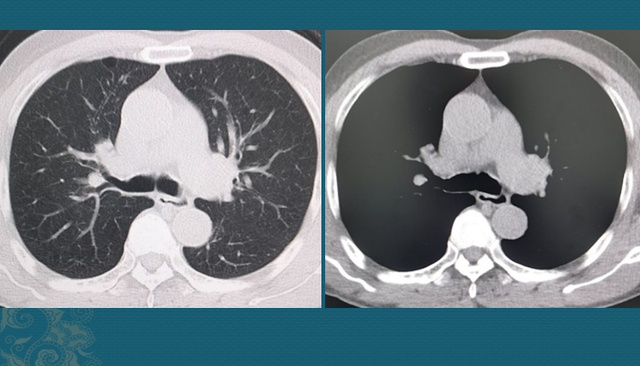

我们先不争论这些,看看这个病人的CT片:

右侧肺门区一个不规则肿块,最大径线4.6cm,远侧肺组织里有一些小点片状炎症,这是由于肿瘤堵塞气道,引起的壅闭 性肺炎。

从生长速率 上看,肺鳞癌通常比腺癌更快,破损 力更大(某些低分化腺癌也很快)。我们搜索这位病人既往的检查资料,发现他2年前由于 伤风、咳嗽、发烧做过一次胸部CT,其时的支气管和肺脏是完全正常的: